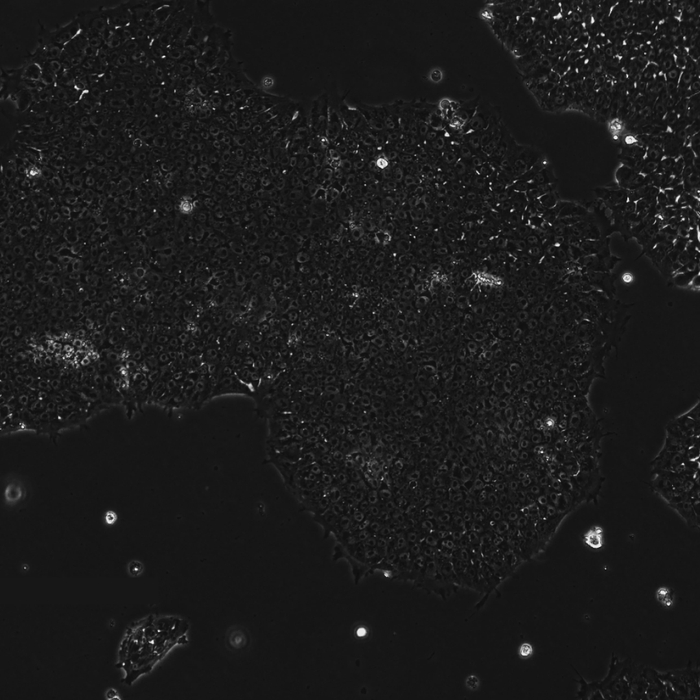

下面这三张图展示的是,OpenAI设计的蛋白质能更高效地诱导干细胞重编程:

使用RetroSOX与RetroKLF变体(结合OCT4, MYC)重编程10天后,出现了大量具有紧凑、圆形形态的集落,这是细胞迈向iPSC状态的典型特征